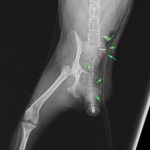

鎮痛剤で跛行が改善しないワンコの精査依頼がありました。CTでは股関節(主に腸骨)に骨融解像が確認されました。細胞診では悪性腫瘍と暫定診断が行われました。除痛のため半側骨盤切除で対応しました。後肢を失うことは大変辛いことですが、ワンコは痛みがなくなり快適に過ごせているそうです。一見、整形外科に見えても高齢犬には腫瘍が隠れていることがあるのでCTによる精査は大変有効です。